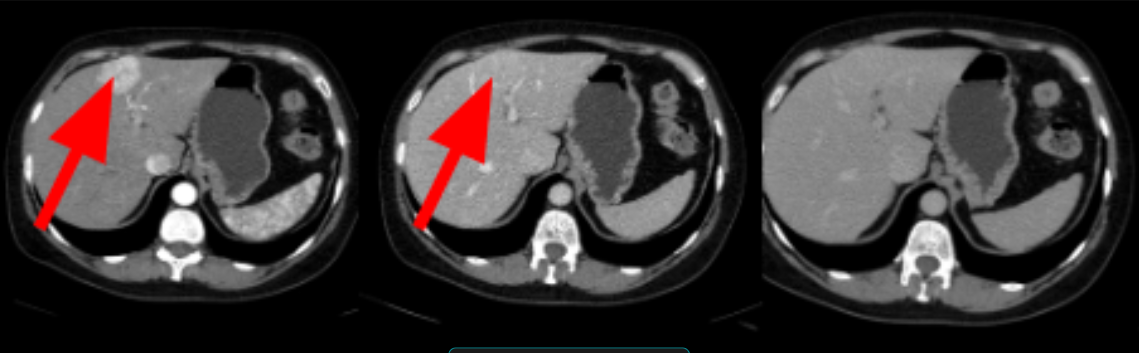

HIPERPLASIA NODULAR FOCAL

lesão com marcado realce hipervascular (realça mais que o parênquima hepático adjacente) na fase arterial e presença de cicatriz central que usualmente apresenta realce tardio.